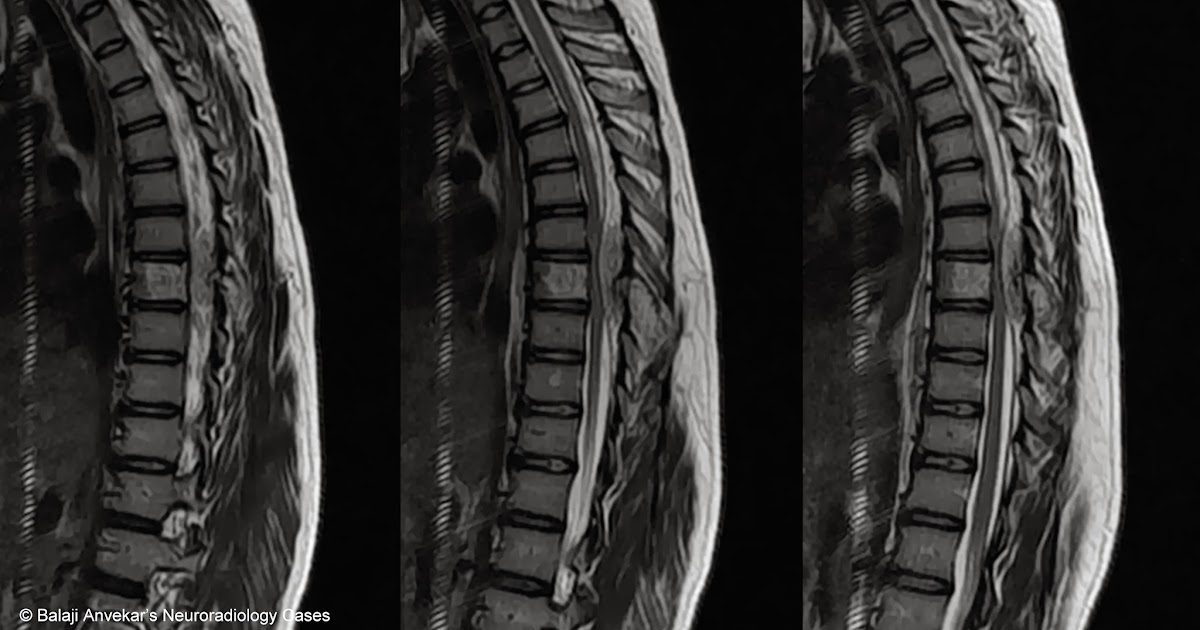

Dr Balaji Anvekar FRCR Spinal epidural lesion causing cord compression MRI Cord Compression Mri Protocol Use of a compartmental spinal mri approach in patients with suspected nontraumatic spinal. Mri with and without gadolinium is the modality of choice for diagnosing spinal hematoma, as it will demonstrate both the hematoma and any. Attention to the transverse axial imaging is important to. Spinal cord compression (scc) is a surgical emergency, usually requiring prompt surgical decompression to prevent. Cord Compression Mri Protocol.

Dr Balaji Anvekar FRCR Spinal epidural lesion causing cord compression MRI Cord Compression Mri Protocol Timely management of acute spinal cord injury is based on a combination of accurate clinical exam and advanced imaging to detect neurologic,. Attention to the transverse axial imaging is important to. Mri with and without gadolinium is the modality of choice for diagnosing spinal hematoma, as it will demonstrate both the hematoma and any. Spinal cord compression (scc) is a. Cord Compression Mri Protocol.